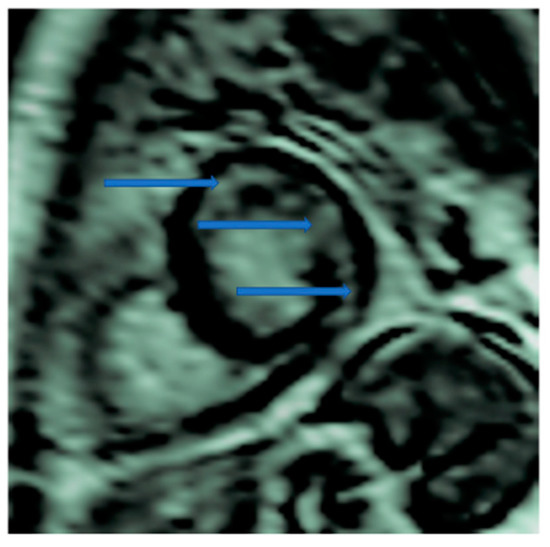

4.5. Myocardial Edema-Fibrosis Assessment

- Mavrogeni, S.; Pepe, A.; Nijveldt, R.; Ntusi, N.; Sierra-Galan, L.M.; Bratis, K.; Wei, J.; Mukherjee, M.; Markousis-Mavrogenis, G.; Gargani, L.; et al. Cardiovascular magnetic resonance in autoimmune rheumatic diseases: A clinical consensus document by the European Association of Cardiovascular Imaging. Eur. Heart J. Cardiovasc. Imaging 2022, 23, e308–e322. [Google Scholar] [CrossRef]